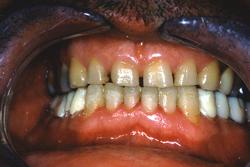

Vue finale

Avant.

Après avec augmentation de la DVO de 6 mm.